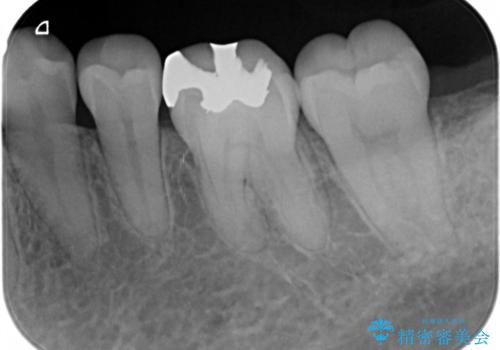

- 大きく口を開けると目立つ銀歯のやり替えをご希望された患者様です。適合のよいセラミックインレーで補綴することで、将来的な虫歯発生のリスクを最小限に抑え、機能面でも安心して使っていただけるようにしました